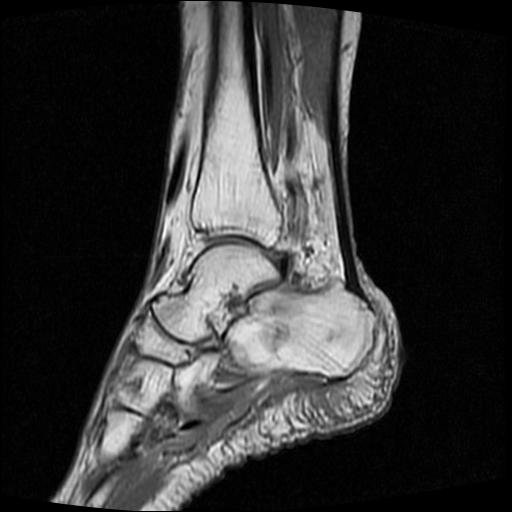

标题: MRI0968:女性,70岁,跟骨信号异常 [打印本页]

标题: MRI0968:女性,70岁,跟骨信号异常

女性,70岁,右侧跟骨疼痛2个月,负重时加剧,不负重时不疼。

胫骨下段,跟骨、距骨可见斑片状异常信号区;考虑:转移瘤

考虑  跟骨骨髓炎

考虑: 跟骨骨髓炎.

跟骨病灶呈片状,边界模糊,可否考虑隐匿性骨折呢?

跟骨长t1长t2信号异常,边缘模糊(肿瘤一般边界清楚,故肿瘤不考虑),压脂像呈高信号--骨髓水肿(炎症?)。